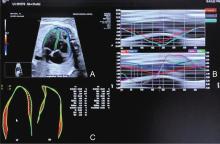

Figure 3

Determination of the cardiac cycle. This figure shows the determination of the right ventricular cardiac cycle to get the annular movement in M-mode by drawing a line perpendicular to the annulus of the right ventricular chamber in the four-chamber view. The cardiac cycle from end-diastole to end-diastole between two troughs is marked on the M-mode graph along with the end-systole. (Images were acquired on E10 Voluson ultrasound machine and analysed using FetalHQ software)"